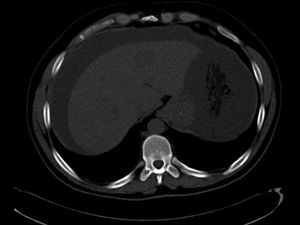

A 37-year-old Lebanese male with no significant past medical history initially presented with an increase in abdominal girth over a few weeks with worsening shortness of breath, nausea, and intermittent vomiting.